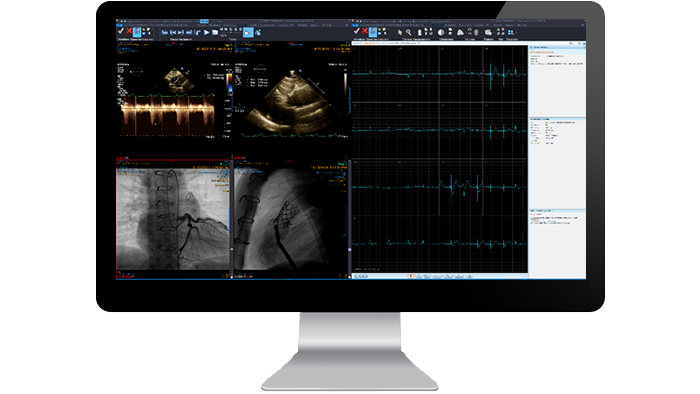

Cardiology

Provide a single, consolidated workspace that streamlines access to cardiology images across locations and modalities for fast diagnosis, reporting, storage and distribution of clinical data. Our web-based picture archiving system consolidates review of echocardiography, cardiac cath, ECG, nuclear cardiology and hemodynamic results with easy comparison of priors to improve patient care.

ECG Viewer application

Embedded application to view ECG waveform with configurable lead display layout. Comparison of prior ECG waveform is supported as well as measurement tools like Line and Caliper.

Cardiovascular reading workflow

Cardiac review and analysis tools provide cross-sectional views of the heart axis, four chamber views, as well as panoramic and cross-sectional views of cardiac arteries. The calcium-scoring module helps you analyze calcified plaque, while the cage-removal function removes anatomy not required for cardiac viewing. Multiframe display includes nuclear medicine, ultrasound and angiography images.

Digital subtraction angiography

Digital subtraction enhances visibility of blood vessels in bony or dense tissue environments. Embedded application to review diagnostic and interventional X-ray angiography to visualize blood vessels.